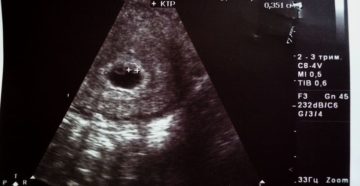

Узи на 7 неделе беременности: фото, размер плода Большинство женщин на определенном этапе своей жизни…

7 недель беременности: тревожные симптомы и болевые ощущения, состояние женщины и развитие плода, анализы и…